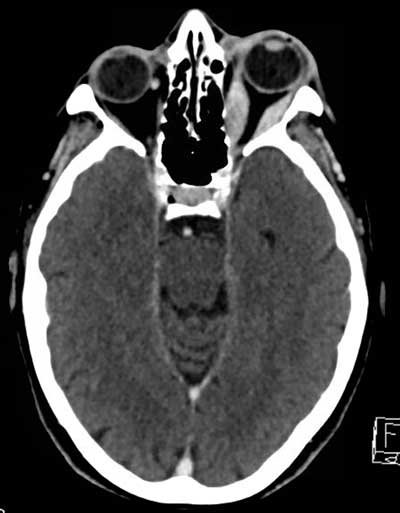

Figure 1

Contrast-enhanced axial CT of the brain shows fusiform and contrast-enhancing thickening of the left lateral and medial rectus muscles.